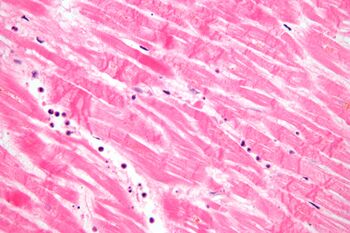

The most commonly used stain in histology is a combination of hematoxylin and eosin (often abbreviated H&E). Hematoxylin is used to stain nuclei blue, while eosin stains the cytoplasm and the extracellular connective tissue matrix of most cells pink. There are hundreds of various other techniques which have been used to selectively stain cells. Other compounds used to color tissue sections include safranin, Oil Red O, congo red, silver salts and artificial dyes. Histochemistry refers to the science of using chemical reactions between laboratory chemicals and components within tissue. A commonly performed histochemical technique is the Perls' Prussian blue reaction, used to demonstrate iron deposits in diseases like Hemochromatosis.[2]

Recently, antibodies have been used to stain particular proteins, lipids and carbohydrates. Called immunohistochemistry, this technique has greatly increased the ability to specifically identify categories of cells under a microscope. Other advanced techniques include in situ hybridization to identify specific DNA or RNA molecules. These antibody staining methods often require the use of frozen section histology. These procedures above are also carried out in the laboratory under scrutiny and precision by a trained specialist medical laboratory scientist (a histoscientist). Digital cameras are increasingly used to capture histopathological images.